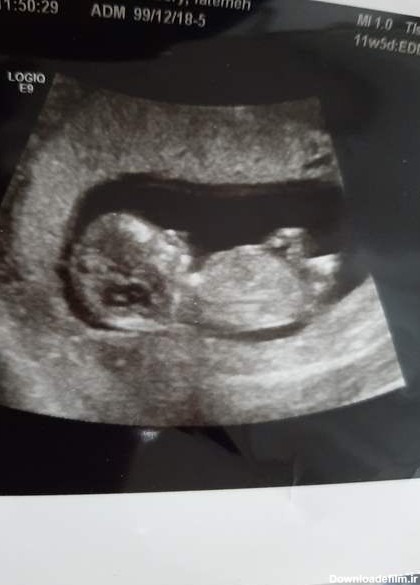

پسره ؟؟؟ این عکس سونوی هفته ۱۲ و ۴ روز من هست ممنون میشم در مورد جنسیتش نظر بدین